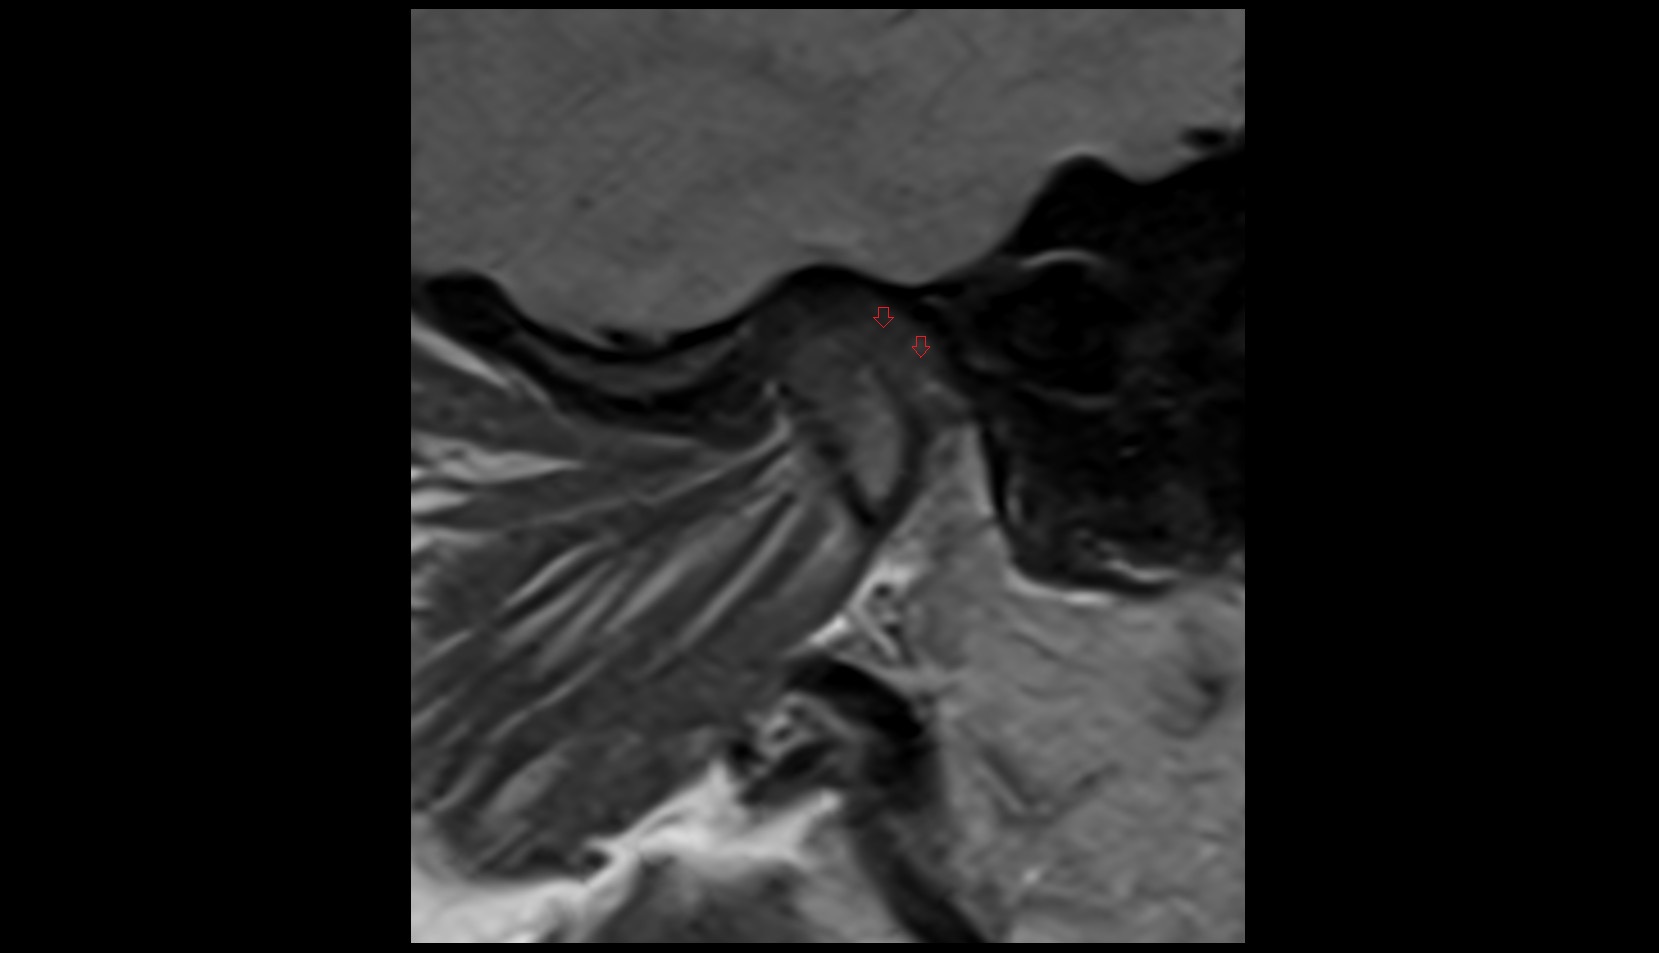

- Temporomandibular joint

- Articular disc of temporomandibular joint

- Articular eminence

- Mandibular condyle

- Mandibular fossa